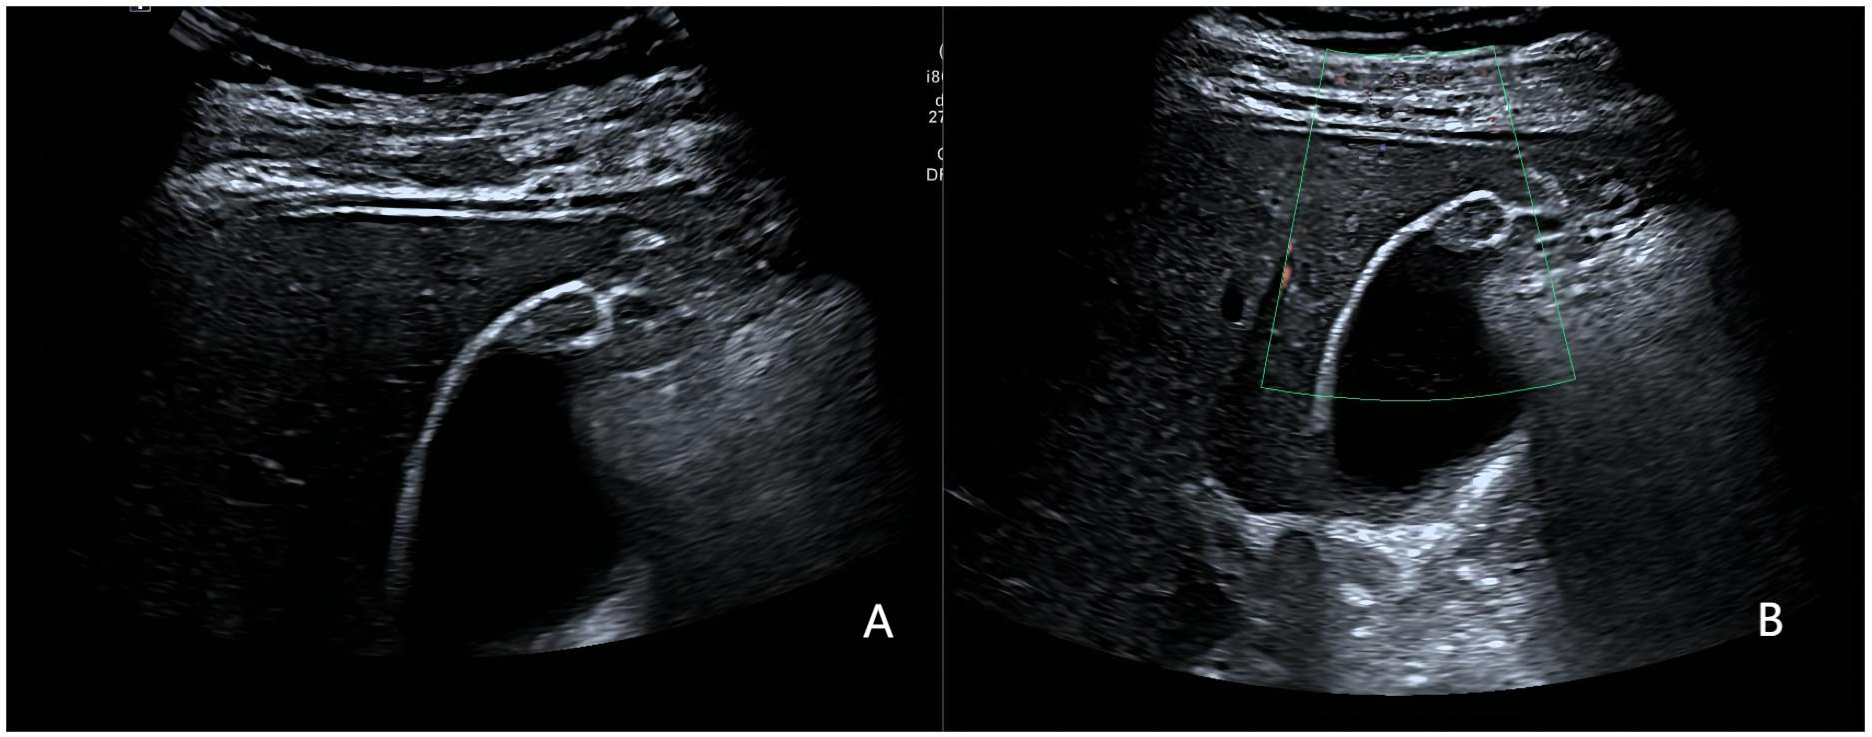

Figure 5

www.frontiersin.org

Figure 5 A 52-year-old man with a pathologically proven adenocarcinoma. (A) Focal thickening of the base of the gallbladder, with no stratified appearance, and loss of interface with the liver.; (B) CDFI=II. Based on a consensus review of the sonographic findings, the lesion was categorized as GB-RADS 4, GB-RADS+CDFI 4.